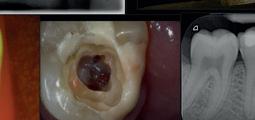

Rise of the Internet dental diagnosis

From the bizarre, and the ridiculous to the positively dangerous, online ‘dentistry’ has been blooming in popularity

As of January 2024, there were 5.35 billion internet users worldwide, which amounted to 66.2% of the global population. Of this total, 5.04 billion, or 62.3% of the world’s population, were social media users. 1

It is hard to get an exact number of those who are regularly performing dentistry on themselves. However, in February, polling by the British Dental Association (BDA) revealed that 82% of dentists are treating gruesome cases of DIY dentistry. 2

The internet and social media are part of our everyday lives. It is easy to understand why some people are turning to the internet for advice. The ongoing dental access crisis that has been building over the last few years, has left many desperate for dental advice wherever they can get it.

Why not get it at the touch of a phone screen?

Like a lot of the information that can be found on the internet, this advice may not be coming from a dental professional. At best, the advice may be useless. At worse, it could actually damage a patient’s teeth and gums.

what are the biggest internet issues?

Reams of misinformation and wrong claims abound on the internet. You can visit sites such as TikTok to investigate all the ways people are putting their smiles in danger.

Influencers are recommending rubbing fruit like strawberries and lemons on their teeth constantly to whiten them. Filing their teeth with a nail file so they look straighter. Using nail glue to fix their loose teeth to the gums.

These examples are certain to send a shudder of horror through any dental professional when their patients admit to attempting them. These types of DIY dentistry can cause permanent damage to patients’ mouths.

More importantly, these practices can cause pain and be costly to correct, putting pressure on the dentist to perform miracles and undo the damage.